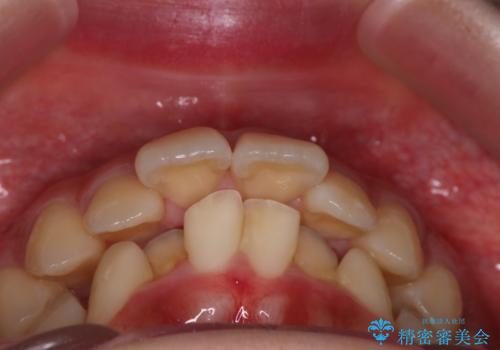

- 前歯の突出を主訴に来院されました。

アンカースクリューとインビザラインを用いて遠心移動を行うことでできる限り前歯を下げて叢生の改善を行いました。